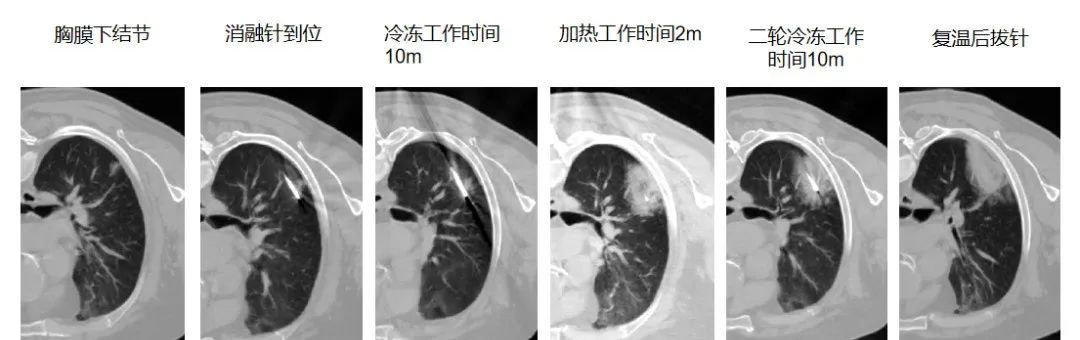

冷热复合式消融技术的独特之处首先体现在它以外科技术为核心,巧妙地融合了冷热复合式消融理念。在治疗过程中,科室依托先进的多学科协作诊疗(MDT)模式,组织多领域专家对患者的肿瘤特征、全身状况以及治疗耐受性进行全面而细致的综合评估。这种精准的评估体系能够根据患者的具体情况,在微创腔镜手术、介入消融等多种治疗策略中,为患者量身定制个体化的治疗方案。

针对肺部多发结节治疗难题,天津医科大学总医院肺部肿瘤外科创新推出 “胸腔镜微创 + 冷热复合式消融” 的 “杂交手术” 模式。该技术避免传统手术对肺功能的损伤,让无法单一术式根治的患者获得更彻底治疗,目前占科室消融治疗总量 10%,实现肺功能保护与肿瘤控制率双提升。在此基础上,科室将冷热复合式消融技术应用于局部晚期肺部肿瘤的姑息治疗,与靶向、免疫、放疗等手段结合,形成 “局部 - 全身” 全程化管理模式,有效缓解患者症状、控制病情、延长生存期。